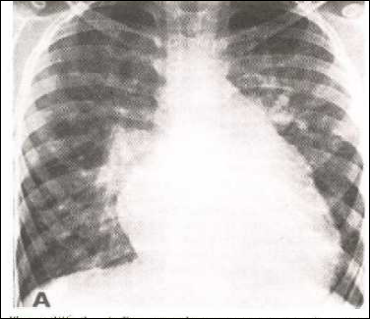

肺血多

大型室间隔缺损

心胸比例增大,以左室大明显;

肺动脉段凸出